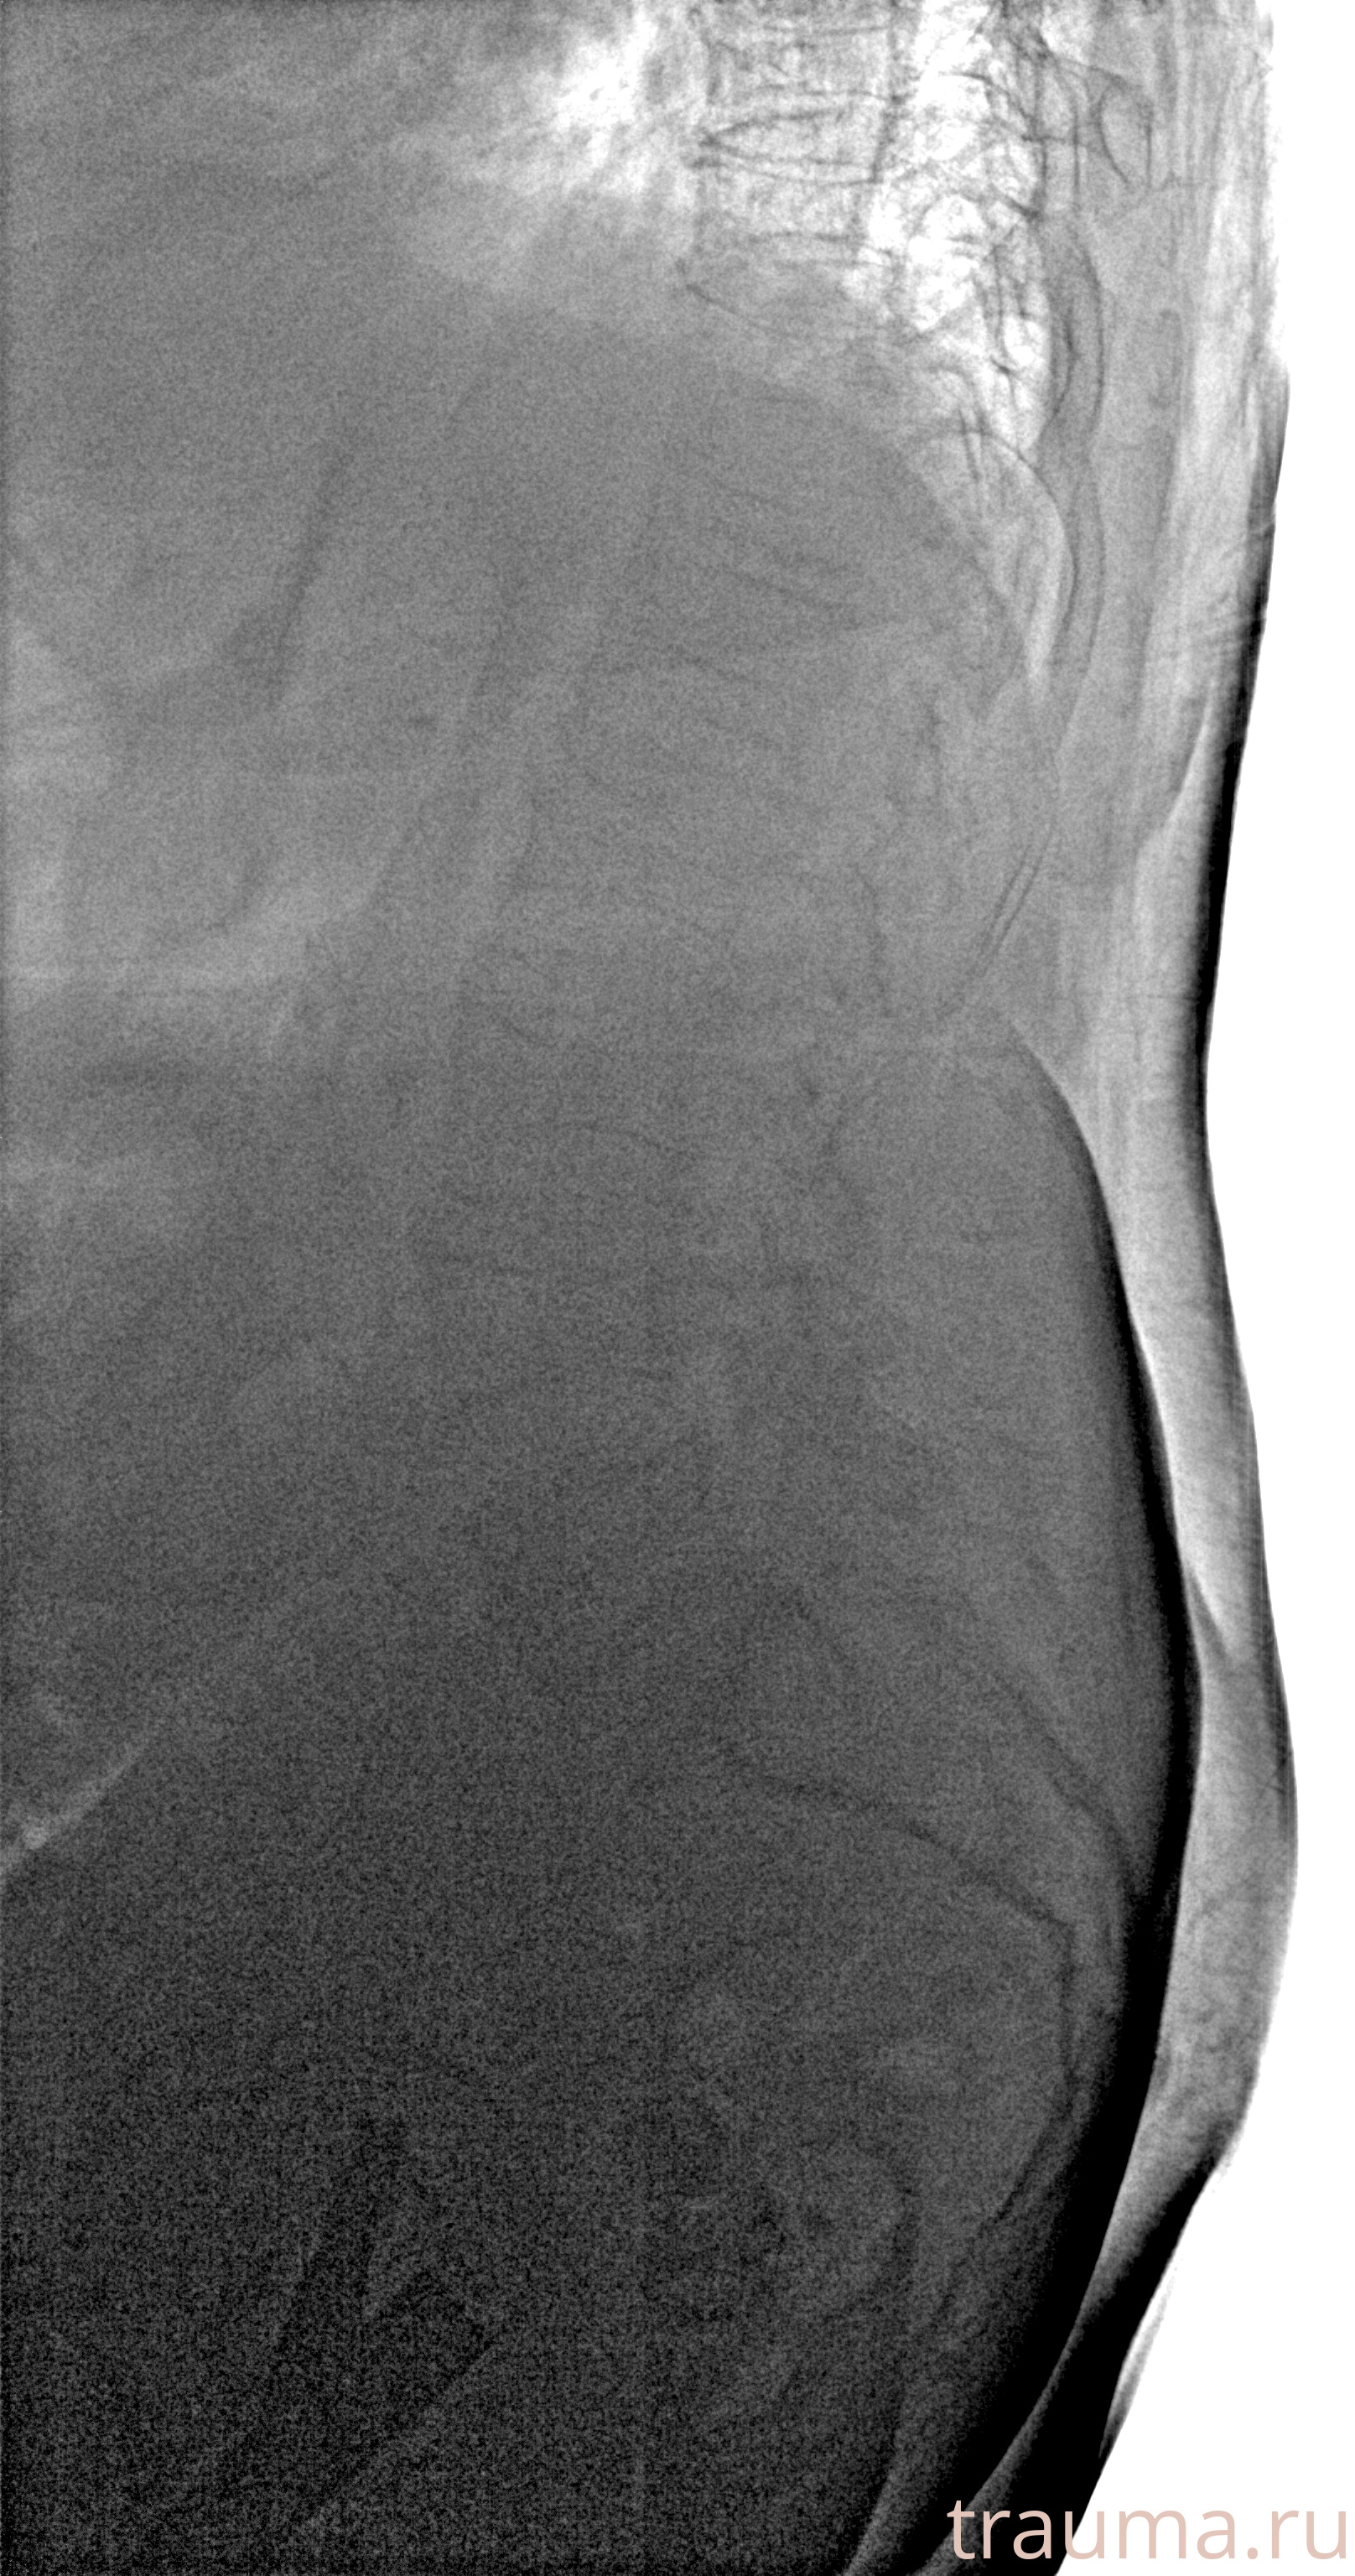

/  Касимова

Рентгенограммы

Рентген на дому: по вашему адресу приезжает врач-рентгенолог, травматолог-ортопед с мобильным рентгеновским аппаратом, проводит диагностику травмы или заболевания, делает необходимые рентгенограммы, дает рекомендации по дальнейшему лечению. Получить качественные снимки в домашних условиях возможно благодаря уникальной методике, разработанной МосРентген Центром для института  Склифосовского